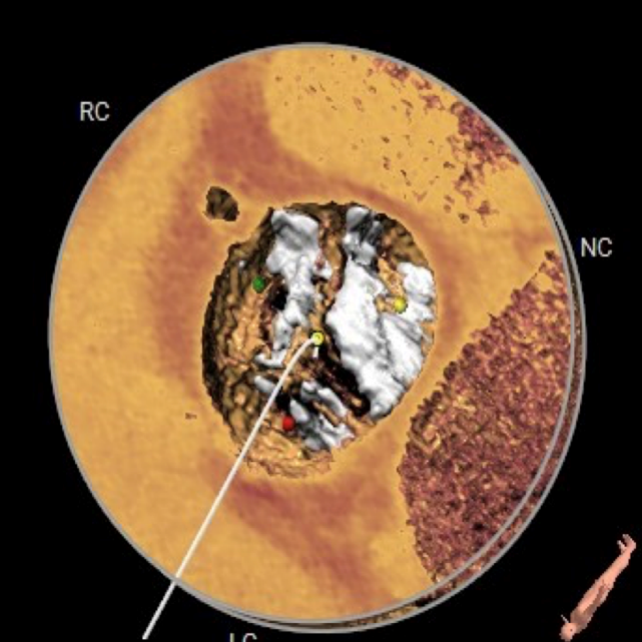

该患者为一例重度AS患者,EF值0.1,手术风险极高。Type0型二叶式主动脉瓣,瓣叶重度钙化并分布不均,瓣叶增厚明显。主动脉瓣环水平夹角66度,横位心。瓣口形态不规则,呈火山口状。假体瓣膜释放后有位移可能。

CT数据显示该患者为Type0主动脉瓣。

主动脉瓣瓣环周长97.1mm,平均周长径 30.9mm,SOV:34.8mm*47.5.3mm*42.4mm,瓣叶增厚,瓣上钙化分布不均,瓣环水平夹角66°。

钙化分布:HU850钙化积分881mm³